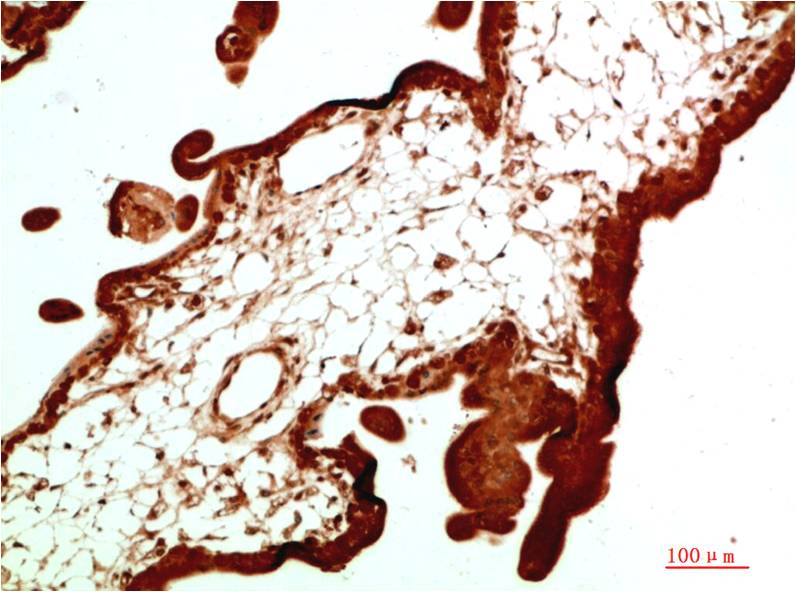

c-Jun Mouse Monoclonal Antibody(4G10)

Applications :IHC

| Recommended dilutions: | IHC 1:100-200 |

| Specificity: | The c-Jun Mouse Monoclonal Antibody can detects endogenous c-Jun proteins. |